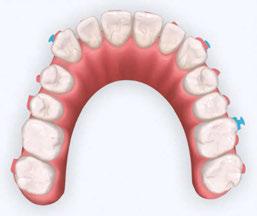

Interproximal recontouring is a crucial component of orthodontic treatment that involves the careful reshaping of tooth surfaces where they touch. This procedure is essential for creating space for teeth movement, improving alignment, and enhancing overall smile esthetics.

Several techniques can be employed for interproximal recontouring, each suited to different clinical situations.

in coarse, medium, and fine grits (Figure 7), come in 4 mm and 2.5 mm widths to accommodate various clinical scenarios. The non-diamond coated center section of the strip allows for easy placement in tight contact areas.

To open a contact, the diamond abrasive surface of the strip is positioned at the tooth’s contact point. In posterior teeth, the strip is maintained parallel to the mesial or distal surface and gently pulled buccally and lingually to create a flat proximal surface. The strip is then reversed to modify the opposing proximal surface. To prevent food traps and facilitate subsequent orthodontic treatment, it is essential to avoid excessive reduction of the proximal contact area.

In the anterior region, where recontouring is aimed at correcting tooth width at the contact area, the strip is curved to follow the buccal-lingual curvature of the tooth (Figure 8B). The process is repeated on the adjacent tooth (Figure 8C).

When dealing with severe crowding, especially in the mandibular anterior, it is crucial to orient the strip to match the tooth’s proximal orientation being modified (Figure 9). This ensures a natural appearance following orthodontic treatment.